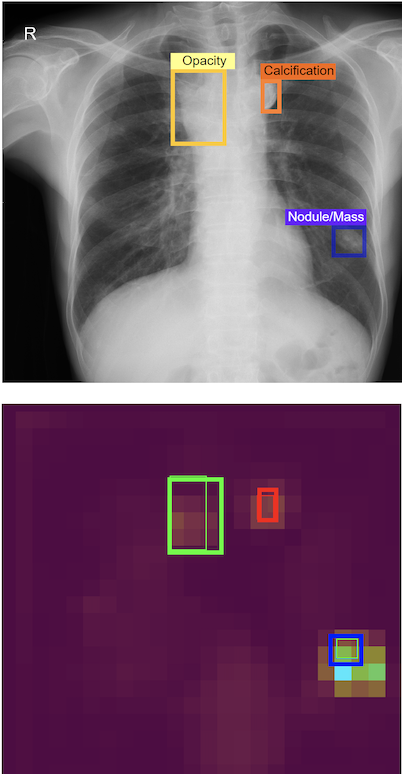

The proposed framework includes two major components. First, an image-level classification network [13] accepts a CXR scan as input and predicts whether it could be normal or abnormal. Second, a lesion-level detection network [13, 14] receives an abnormal CXR scan as input from the classifier and provides the location of abnormal findings via bounding box predictions. The core of the VinDr-CXR system is based on state-of-the-art DL networks for image classification and object detection tasks. VinDr-CXR was trained on 51,485 CXR scans with radiologist-provided bounding box annotations [4]. The actual impact of the VinDr-CXR was evaluated through a reader study (N = 400). The inter-rater agreement among radiologists as well as the rate of agreement between VinDr-CXR and radiologists are then assessed the Cohen’s Kappa metric.

We recruited a group of six board-certified radiologists from 108 hospital (H108) and Hanoi Medical University (HMUH) to participate in our observer performance test. The reader study was conducted in two sessions. In the first session, participating readers read the CXR scans independently without the VinDr-CXR assistance. During the second session, the readers re-evaluated all CXR scans with the assistance of the VinDr-CXR. Specifically, the radiologists were provided the VinDr-CXR predictions in the form of bounding boxes, which locate abnormalities. They considered the model’s prediction and modified the diagnostics. Our experiments showed that in the second read, with the support of the VinDr-CXR system, agreement among three H108’s radiologists was moderate with a Fleiss’ Kappa of 0.545 (0.465, 0.625), corresponding to a 3.0% improvement in Fleiss’ Kappa compared to the first read. Additionally, we found that the rate of VinDr-CXR agreement with the participating radiologists was slightly higher than the rate of agreement among radiologists. The agreement between each radiologist and the system was remarkably increased by 3.3% in mean Cohen’s Kappa.